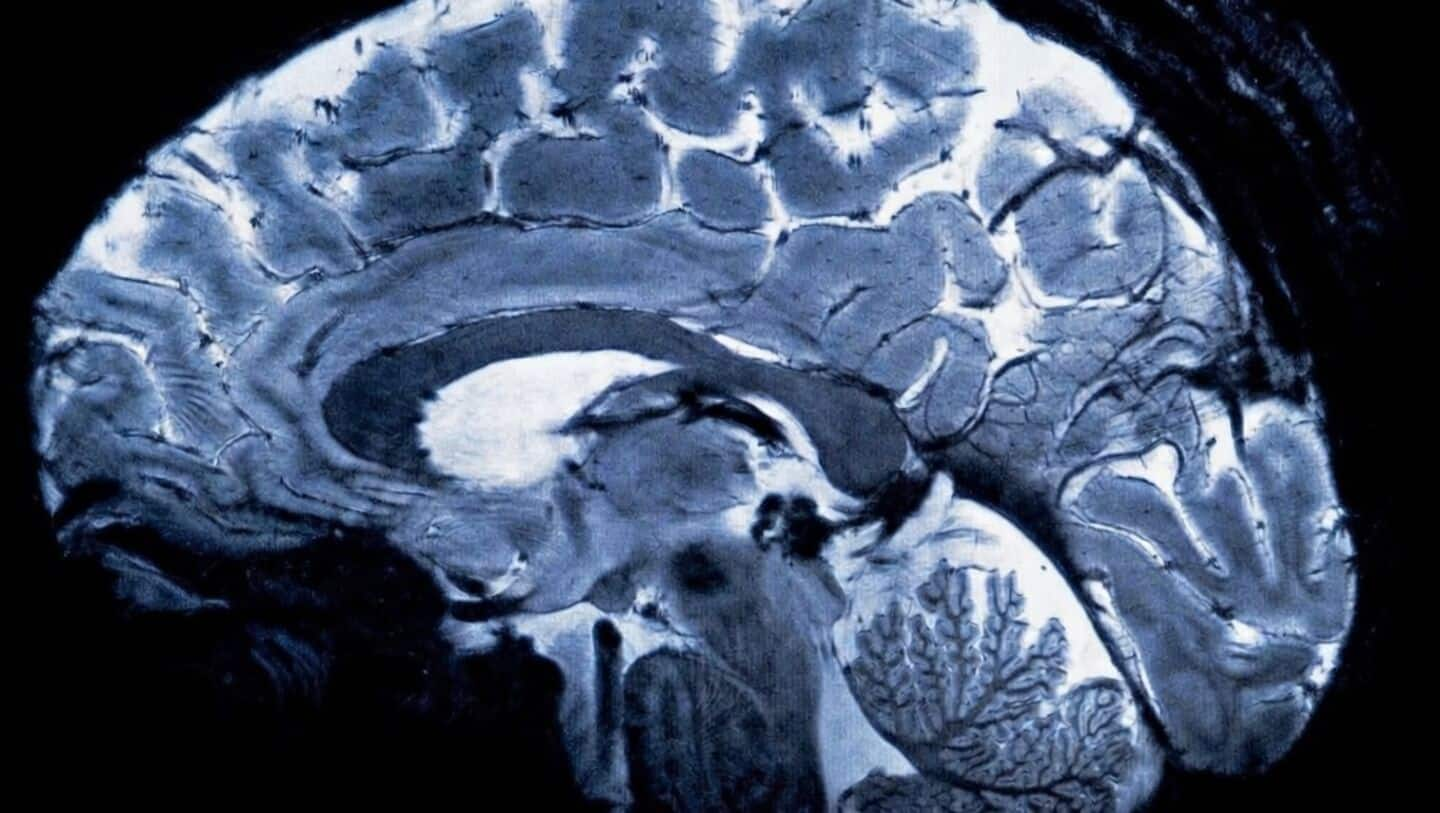

Northwestern University researchers may have found a game-changer for treating schizophrenia's toughest symptoms.

Their new study identifies a biomarker linked to cognitive symptoms, and introduces a fresh approach that could actually help with those cognitive struggles.